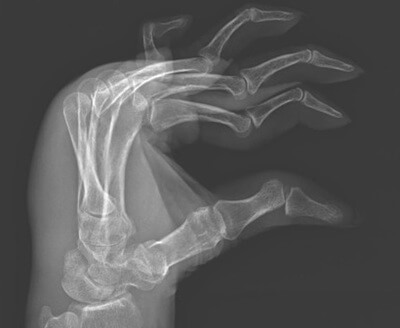

A swan neck deformity is a common condition where the fingers bend abnormally.

Swan neck deformity is a degenerative finger condition where:

This creates the classic “swan neck” appearance, similar to the curve of a swan’s neck, hence the name. It is the opposite of a boutonniere deformity.

Swan neck disease affects the balance of tendons and ligaments that control finger movement. When this balance is lost, the finger can no longer straighten and bend normally. Over time, the deformity may become fixed and difficult to correct.